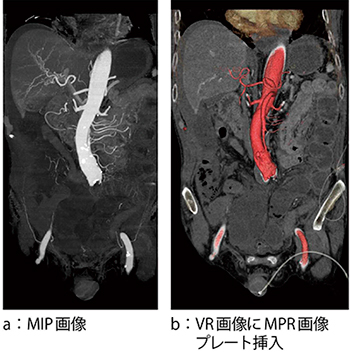

症例3は,上腸間膜動脈の血栓である。絞扼性イレウスを疑われ,腹部dynamic CTを施行した。造影早期相および遅延相において,肥厚した腸管の造影能の低下を認めた7),8)。骨除去された末梢血管まで確認できるMIP画像(図7 a)を用いて,血管の走行および閉塞している血管の同定を行った。上腸間膜動脈の起始部での閉塞が確認でき,VR画像にMPR画像をプレート挿入(図7 b)して腸管や血管の走行を再確認し,緊急外科手術が行われた。

図7 症例3:上腸間膜脈動脈の血栓の描出

末梢までの血管描出にはMIP画像が適するが,立体的な位置関係はVR画像が適する。VR画像上にMPR画像プレートを挿入すると,実質臓器や周辺組織との位置関係を把握できる。